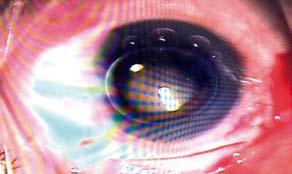

A la hora de considerar los lentes intraoculares premium para pacientes con glaucoma y sospechosos de padecerlo, la decisión suele depender de la gravedad de la enfermedad. Ciertas opciones premium pueden exacerbar los síntomas visuales preexistentes. Por ello, los oftalmólogos deben determinar la lente más adecuada en cada caso, sopesando tanto las preocupaciones visuales como las relacionadas con el glaucoma. Aquí, los expertos debaten las opciones de LIO que consideran en estos casos y cómo explican a los pacientes las limitaciones relacionadas con el glaucoma.

Figura 1. Fotografía del nervio óptico de un paciente con glaucoma de ángulo abierto leve y campos visuales casi normales. La agudeza visual inicial era de 20/40 OU. Fotografía: Constance Okeke, MD.

Figura 2. El paciente de la figura 1 se sometió a una cirugía combinada de cataratas y MIGS con implantación de PanOptix y goniotomía Streamline. La agudeza visual postoperatoria mejoró a 20/20 en distancia e intermedia, y a J1+ en cerca. La PIO fue de 14 y 12 mmHg con un objetivo de 15 mmHg. La carga de gotas se redujo de tres medicamentos a uno. Foto: Constance Okeke, MD.

Figura 3. Un ejemplo de un mal candidato para un LIO multifocal. El ojo derecho de este paciente está bastante sano, mientras que el izquierdo presenta una enfermedad significativa. Aunque el ojo derecho está más sano y no presenta pérdida del campo visual, los expertos afirman que existe la preocupación de que acabe como el otro ojo y tenga problemas en el futuro. Fotos: Shivani Kamat, MD.

Figura 4. Paciente con hipertensión ocular sin daño en el nervio óptico. Este paciente es candidato para una LIO multifocal. Fotos: Shivani Kamat, MD.